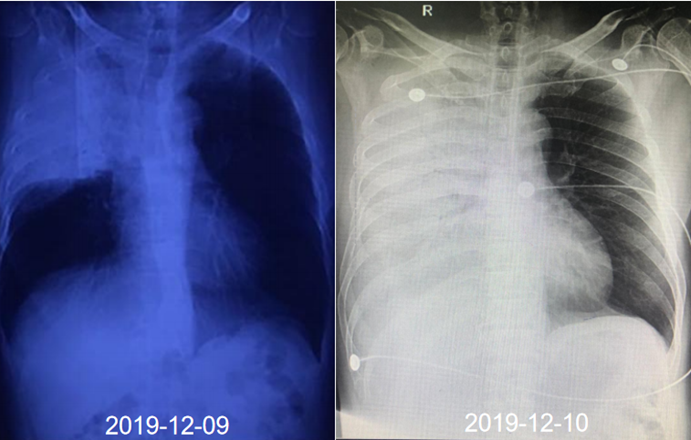

7月4日(患者入院前)胸部CT可见下肺磨玻璃渗出(图1)

图1  患者胸部CT(2019-07-04)

尿军团菌抗原(+)。入院第2天:无创机械通气通气,FiO2 100%;第3天气管插管,有创机械通气,FiO2 100%,PEEP 13 cmH2O。第4天,FiO2 45%,PEEP 8 cmH2O。逐渐降低支持力度,插管第7天撤机,拔管。拔管5天转入普通病房。整个病程中患者发热症状持续14天。患者入院前后胸部影像学变化如图2所示。

图2  患者胸部CT变化